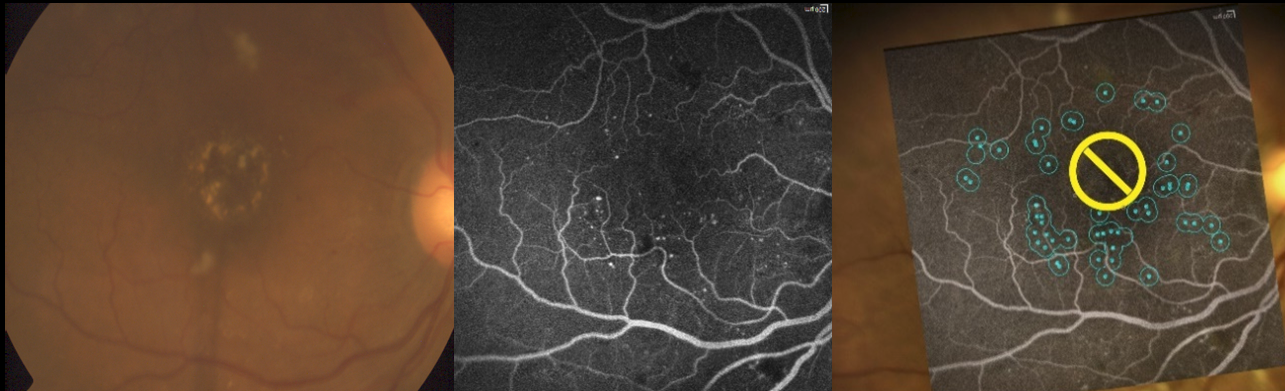

Aparat Navilas

Takiego urządzenia nie tylko w Szczecinie, ale i w całym kraju jeszcze nie było. Navilas to pierwszy cyfrowy system, który pozwala na bardzo precyzyjną rejestrację obrazu dna oka w kolorze i szerszym polu widzenia, wcześniejsze zaplanowanie zabiegu w detalach oraz szybsze i mniej inwazyjne przeprowadzanie laseroterapii.

Nowe urządzenie Pracowni Laserowej II Kliniki Okulistyki Samodzielnego Publicznego Szpitala Klinicznego Nr 2 w Szczecinie to unikalne połączenie lasera oraz funduskamery - jednego z podstawowych narzędzi okulistycznych, za pomocą którego wykonywane jest m.in. badanie dna oka bez użycia preparatów rozszerzających źrenice. Aparat NaviLas służy do obserwowania zmian chorobowych siatkówki, jest pomocny w planowaniu terapii laserowej oraz w kierowaniu lasera w precyzyjnie wybrany obszar oka.

Obecne w okulistyce trendy ograniczają destrukcyjny efekt interwencji laserowej. Celem jest subtelne i ukierunkowane leczenie tylko miejsc patologicznych przy użyciu urządzenia z nawigowaną wiązką laserową oraz ograniczenie uszkodzenia termicznego tkanki dzięki zastosowaniu trybu mikropulsowego – tłumaczy prof. dr hab. n. med. Wojciech Lubiński, lekarz kierujący II Kliniką Okulistyki w Samodzielnym Publicznym Szpitalu Klinicznym Nr 2 PUM w Szczecinie. Zabiegi z zastosowaniem systemu NaviLas to nowa era leczenia i są już powszechną praktyką stosowaną na świecie. A teraz takie leczenie stosujemy w naszej kliniki w Szczecinie – dodaje.

Zastosowanie w urządzeniu technologii mikropulsów umożliwia dostarczenie do oka mniejszej ilości energii, co pozwala zmniejszyć uszkodzenie tkanek.

Laser służy do leczenia chorób siatkówki mówi prof. Lubiński – System NaviLas może być wykorzystywany m.in. w terapii ocznych powikłań cukrzycowych, po zakrzepie naczyń żylnych siatkówki, także przy zmianach na obwodzie dna oka, jak np. zwyrodnienia, przedarcia, otwory, odwarstwienia i rozwarstwienia siatkówki.

Fot. SPSK2